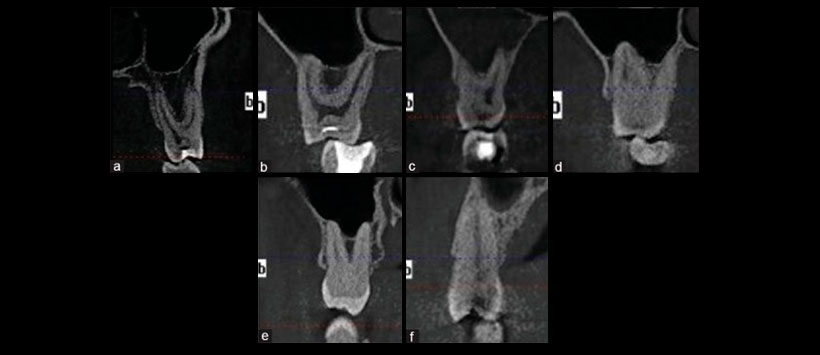

Figura 1 :

La relación vertical entre la pared inferior del seno maxilar y las raíces de los molares superiores.

Figura 2:

La relación vertical entre la pared inferior del seno maxilar y las raíces de los molares superiores en CBCT.